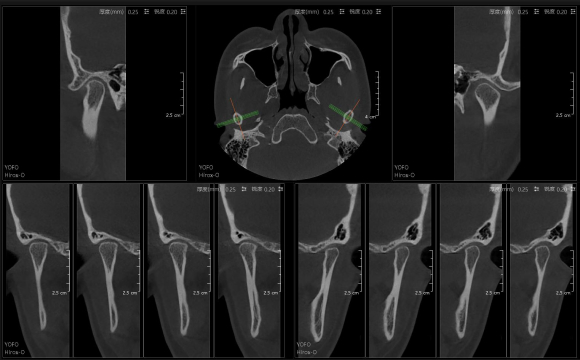

• 3D TMJ視圖

3D TMJ視圖

只需一次單圈掃描即可獲得CT、數字全景和3D正/側位影像,

并能同時生成3D TMJ視圖 提高診療效率,避免過度檢查,減少患者所受的輻射